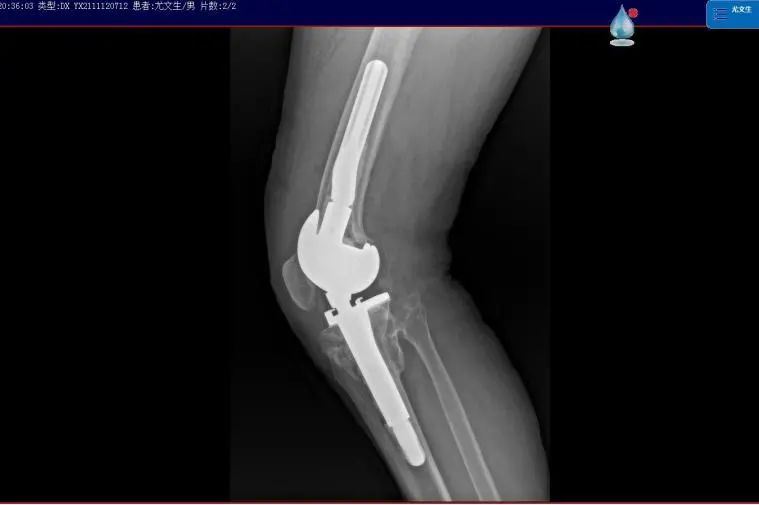

▲术后影像

11月10日,受益于“我为群众办实事”实践活动——“晋江市髋膝关节置换救助工程”项目,尤大叔入院进行手术治疗??悸堑交颊呦ス亟谘现夭晃榷?、韧带功能丧失,上海市第六人民医院骨科副主任、主任医师,上海六院福建医院副院长沈灏教授选择了旋转铰链膝对患者行全膝关节置换术。

沈灏指出,人工膝关节置换手术是临床治疗膝关节疾病的常用手段,但膝关节表面置换假体通常适用于绝大多数的初次膝关节置换手术,对于部分严重畸形的膝关节病变及需要翻修的关节而言,普通表面型假体就显得力不从心,需要使用特殊设计的限制型假体来治疗?!靶铝聪プ魑拗菩约偬宓木渖杓?,为复杂手术中面临的严重骨缺损、韧带缺失等问题提供了简便的解决方案,使手术更安全、高效?!?/p>